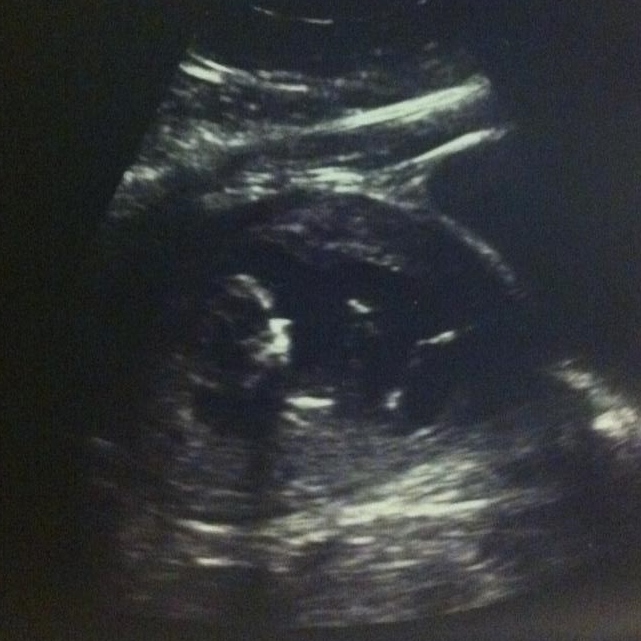

Can anyone guess boy or girl!? There are the best scans I have, I am 18w2d and I'll be having my gender scan in less than 2 weeks!

Sorry, I don't see a nub in either shot :( I hope these two weeks fly by for you!